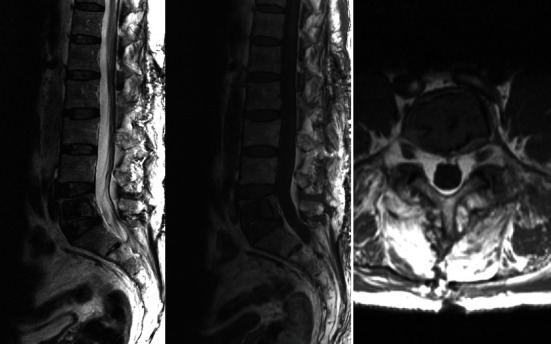

导言:描述一例罕见的成年腰椎椎体单发骨囊肿病例。单发性骨囊肿的定义是含液体的囊性病变。很少有病例描述椎体位置,而不倾向于后弓或椎体。大多数病例采用切除、刮除和/或植骨的方法进行治疗。迄今为止,还没有在椎体位置注射聚甲基丙烯酸甲酯(PMMA)的病例。病例介绍。一名 50 岁的男性患者因腰部疼痛就诊,无外伤史,无神经功能缺损。放射学检查显示,患者在二十年前曾因 L3 骨折而进行过腰椎关节置换术,并植入了 L2-L4 器械。计算机断层扫描(CT)显示,溶蚀性病变几乎占据了 L5 的整个椎体,椎间隙不完整,边缘硬化,皮质无破裂。为了避免在进行磁共振(MR)检查时出现伪影,患者移除了之前的钢制器械,并在同一次手术中经穿刺对 L5 椎体进行了活检。磁共振检查结果和活检结果均与单纯骨囊肿相符。最后,通过使用 PMMA 填充病变部位进行了新的干预。5年的随访结果令人满意,没有腰痛,放射学检查结果也是如此,患者恢复了以往的活动能力:结论:脊柱部位的单纯骨囊肿极为罕见。其诊断需要排除其他病变,并通过影像学检查和活组织检查来确定。治疗方法有切除术、刮宫术、植骨填充术或本例中的PMMA填充术。

Introduction: To describe a rare case of solitary bone cyst in the vertebral body of the lumbar vertebra in an adult patient. The solitary bone cyst is defined as a cystic lesion with liquid content. Few cases have been described in the vertebral location without preference for the posterior arch or vertebral body. Most have been treated with resection, curettage, and/or grafting. No case described to date has been treated with polymethylmetacrylate (PMMA) injection in the vertebral location. Case Presentation. A 50-year-old male patient was consulted for lumbar pain with no traumatic history and no neurologic deficit. The radiological study showed lumbar arthrodesis with L2-L4 instrumentation due to an L3 fracture twenty years earlier. Computed tomography (CT) scan showed a lytic lesion occupying practically the entire vertebral body of L5, with incomplete septum and sclerotic edge, without cortical rupture. The previous steel instrumentation was removed, to avoid the presence of artifacts when performing the magnetic resonance (MR), and a biopsy of L5 vertebra was performed via transpedicular in the same act. The MR study findings and biopsy were compatible with the simple bone cyst. Finally, a new intervention was performed by filling the lesion with PMMA. Follow-up at 5 years was satisfactory without lumbar pain as well as the radiological study and with a return to previous activity.